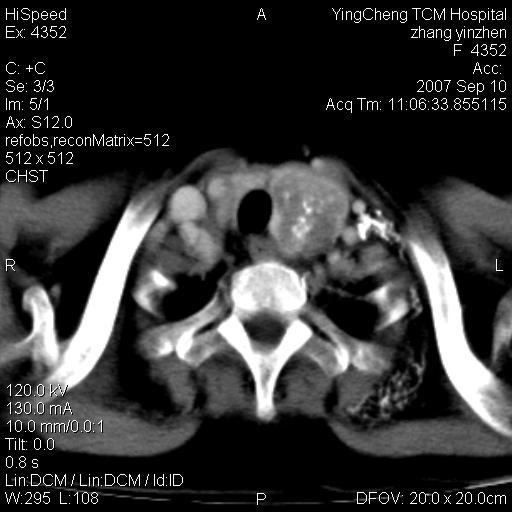

以下是引用卜一在2007-9-18 14:41:00的发言:[br]右肺肿块:毛刺+胸膜凹陷征+供血血管+浅分叶+强化。支持:周围性肺癌 !另:左侧甲状腺腺瘤!

以下是引用夏季在2007-9-18 11:00:00的发言:[br]1。右肺肿块,周围有短毛刺,肺门侧有血管与其相连,胸壁侧有胸膜凹陷征,考虑周围性肺癌 2。左侧甲状腺软组织肿块,内有高密度钙化灶,考虑左侧甲状腺腺瘤。